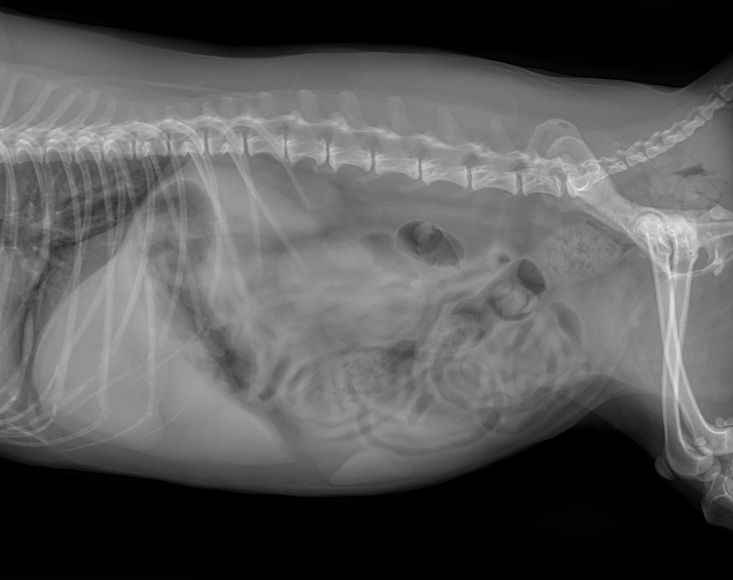

따라서 우선적으로 영상 검사를 통해 주요 원인을 감별하고자 복부 방사선 촬영과 초음파 검사를 진행하였습니다.

방사선 검사에서는 요로결석 등 특이 소견은 확인되지 않았습니다.

그러나 복부 초음파 검사에서 좌측 신장 후극에약 30 × 20 mm크기의 종괴가확인되었습니다.

CT소견–좌측 신장 후극피질 유래의 크기 26mm*40mm의 조영 후 저감쇠성음영–간 좌측 안쪽엽에종괴가보이나 양성 병변 가능성이 더 높음–폐 우측 후엽의 미세결정 음영 CT검사상 전이 가능성은 상대적으로 낮은 상황이었습니다.